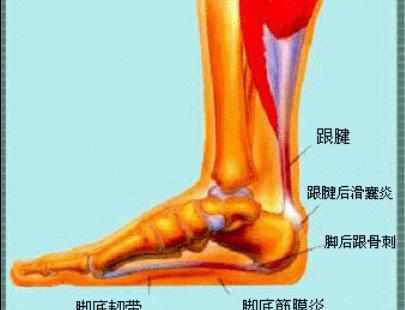

问答 网 : 骨刺微创手术一般一周左右就可以恢复的,如果骨刺出现在负重部位、关节内、腰椎椎管内都会引起疼痛等现象发生最多的部位是跟骨刺,由于跖筋膜老是紧张,引起周围水肿渗出,钙化形成骨刺,行走后经常挤压骨刺导致疼痛微创手术将骨刺切除,创口小,出血少Feb 17, 21 · 我妈妈患有足跟骨刺,能做微创手术痊愈吗人阅读问题描述:(女,21岁)我妈妈患有足跟骨刺,能做微创手术痊愈吗确定是骨刺能做微创手术吗Mar 08, 21 · 你好脚踝长骨刺如果保守治疗没有效果,这个就需要手术治疗,可以行关节镜微创治疗的,这个费用一般1万块钱左右的,平时注意多休息可以贴点膏药呀,啊,做些理疗和针灸这些治疗看看呢。

Jan 09, 15 · 跟痛症(跟骨骨刺、跖腱膜炎)的微创手术治疗:跟痛症只是一个总称,其病因、病理、发病机理目前尚未完全清楚。确认跟痛症首先必须排除跟骨骨髓炎、跟骨骨骺炎、骨结核、骨肿瘤等跟骨疾病,其一般特点是患者多为40岁以上的中老年人,男性较多,体型多比较肥胖Mar 12, 19 · 脚底有骨刺,需要去做手术吗? 如果走路功能受限,可以考虑微创手术治疗。骨刺是足部的保护性增生!不适随诊! 17 asky 追问 微创手术是大手术还是小手术,是要把骨刺磨掉吗? 脚踝骨刺,能切除手术吗患有骨刺,可以小针刀微创手术进行治疗,小针刀微创手术费用在百元左右 1449 相关问题 查看更多>> 你好骨刺手术得多少钱?

老人脚后跟痛是怎么回事 一文给您说清楚 骨刺 滑囊 肌腱 跟腱 网易订阅

足跟骨刺 快懂百科

足跟痛 并非都是骨刺惹的祸 14大 元凶 需警惕 好医术早读文章 好医术 赋能医生守护生命